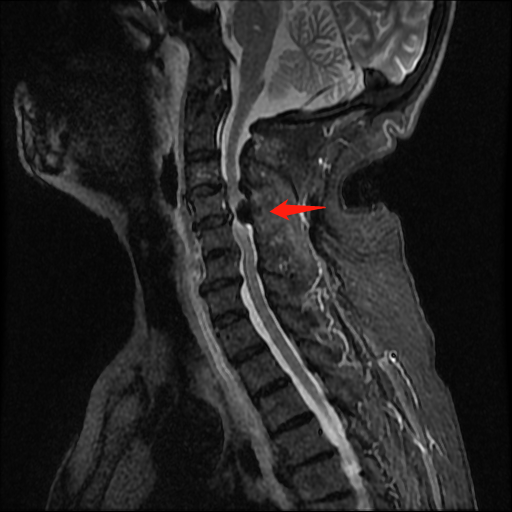

术前颈椎MRI提示:脊髓型颈椎病,属比较严重的颈椎病类型,严重可致残。

术前术后对比

术后复查,颈椎椎管减压范围良好,内环境稳定。